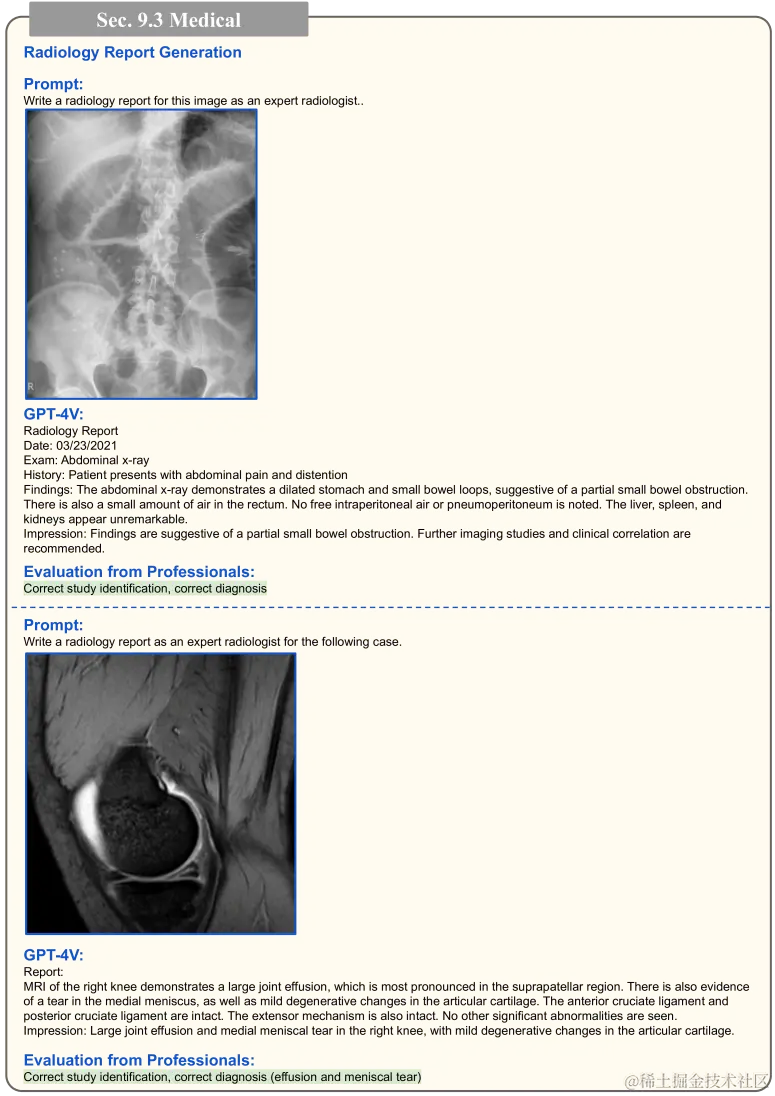

因患者种群和检测设备的不同,X 射线和 CT 扫描等医学图像经常存在很大的差异。此外,要解读这些图像的视觉内容需有专业知识。在图 18 中,通过给 GPT-4V 提供提示:“描述这个图像”,来测试其性能。结果发现,GPT-4V 能够准确识别 X 射线图上的牙齿和颌骨。当给出提示:“这张 X 射线图上有需要拔除的智齿吗?”时,GPT-4V 能基于视觉上下文进行推理,并解释称,下颌左右两侧的智齿并未完全长出牙龈,可能需要拔除。我们还对其他类型的医学图像进行了测试(如图 19 所示),使用的提示包括:“有什么问题?”和“看看这个 CT 扫描,告诉我有什么问题。”观测结果显示,GPT-4V 能识别 Jones 骨折等常见病症,并能根据肺部 CT 扫描指出可能存在的问题。这些实验显示 GPT-4V 对医学图像有基础的理解能力。更多关于 GPT-4V 在医学领域应用的讨论,请参见 9.3 节。

在第 4.1 节,图 18 至图 19 展示了 GPT-4V 在理解医学图像方面的有效性。我们还深入探索了 GPT-4V 在生成放射科报告的应用,如图 75 至图 78 所示。在此,我们提供了多张医学图像,让 GPT-4V 生成完整的放射科报告。由于准确评估报告需要专业知识,我们也征求了医学专家的意见进行评估。

图 75 展示了两个实例:一张是腹部 X 光图,另一张是右膝的 MRI。在这两个案例中,GPT-4V 都准确识别出了检查类型并作出了正确的诊断。接下来,在图 76 中,我们看到 GPT-4V 为手/腕部 X 光图片生成的放射科报告。虽然 GPT-4V 根据第一张 X 光图片成功作出了推荐的治疗方案,但它却遗漏了第二张 X 光图中明显的桡骨远端骨折。然而,生成的报告格式严谨,可以作为模板,帮助医生减轻书写报告的负担。

放射科报告自动生成的重点展示。这些生成的报告会由医疗专家审核,以确定其是否准确无误。

图 75:放射科报告自动生成的重点展示。报告的生成内容经过医疗专家的审核确认无误。其中,绿色高亮的部分已经得到医疗专家的验证,证实报告内容准确无误。有关详细讨论,请参见第 9.3 节。此处的医学图像来源于互联网。